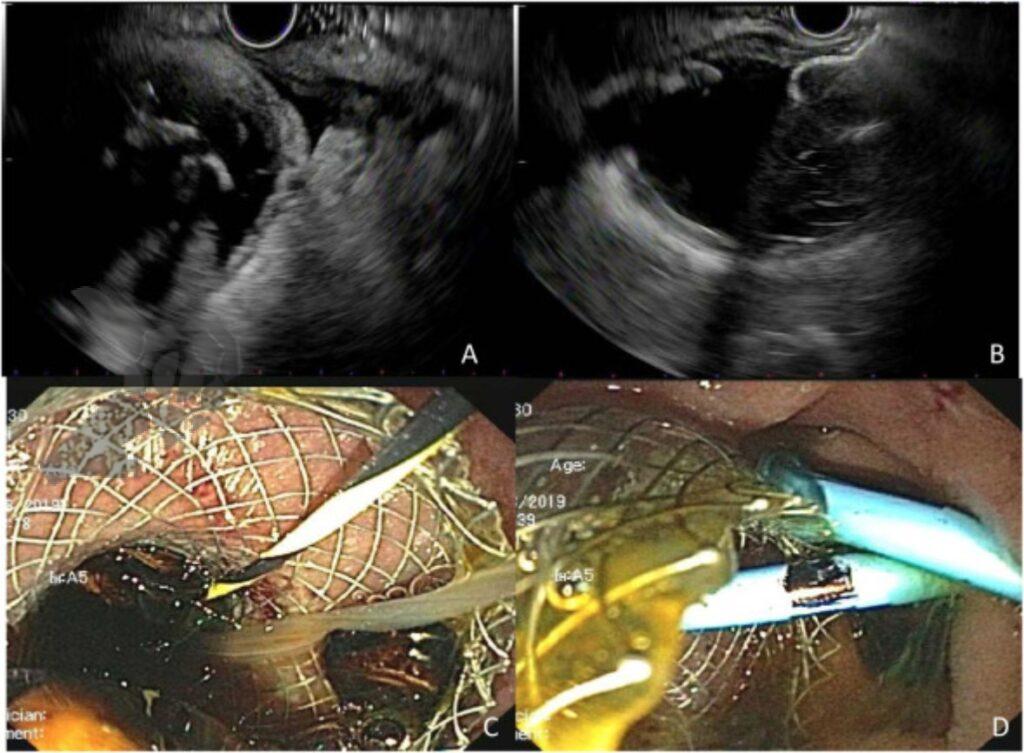

As principais técnicas de drenagem incluem o uso de stents metálicos autoexpansíveis, com destaque para a utilização do stent metálico com aposição de lúmens (LAMS) – clique aqui para saber mais sobre LAMS. Em casos que envolvam dificuldade de posicionamento, vesícula fibrótica ou presença de drenos percutâneos que dificultem a visualização da vesícula, o uso de fio guia pode trazer maior segurança ao procedimento.

A escolha da janela de drenagem é indicada com base na anatomia do paciente e na proximidade das estruturas, sendo a distância de 10 mm entre a parede do TGI e o lúmen da vesícula considerada segura. O acesso pode ser realizado pela janela transgástrica ou transduodenal, sendo que a primeira tem por vantagem a facilidade de acesso cirúrgico ao sítio de punção em caso de colecistectomia posterior, enquanto que o posicionamento no bulbo duodenal pode reduzir a ocorrência de migração da prótese e impactação alimentar. O posicionamento de próteses duplo pig tail no interior da LAMS pode mitigar a ocorrência de sangramento e impactação alimentar2.

A realização de colecistoscopia pode ser indicada após a resolução da colecistite aguda visando a remoção completa dos cálculos da vesícula biliar, nesta ocasião pode-se substituir a LAMS por prótese do modelo duplo pig tail. Outra abordagem, principalmente utilizada em pacientes de alto risco, é manter a LAMS, com realização de nova abordagem apenas caso necesário2.